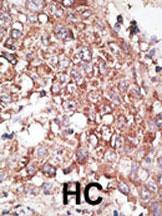

Formalin-fixed and paraffin-embedded human cancer tissue reacted with the primary antibody, which was peroxidase-conjugated to the secondary antibody, followed by DAB staining. This data demonstrates the use of this antibody for immunohistochemistry; clinical relevance has not been evaluated. BC = breast carcinoma; HC = hepatocarcinoma.